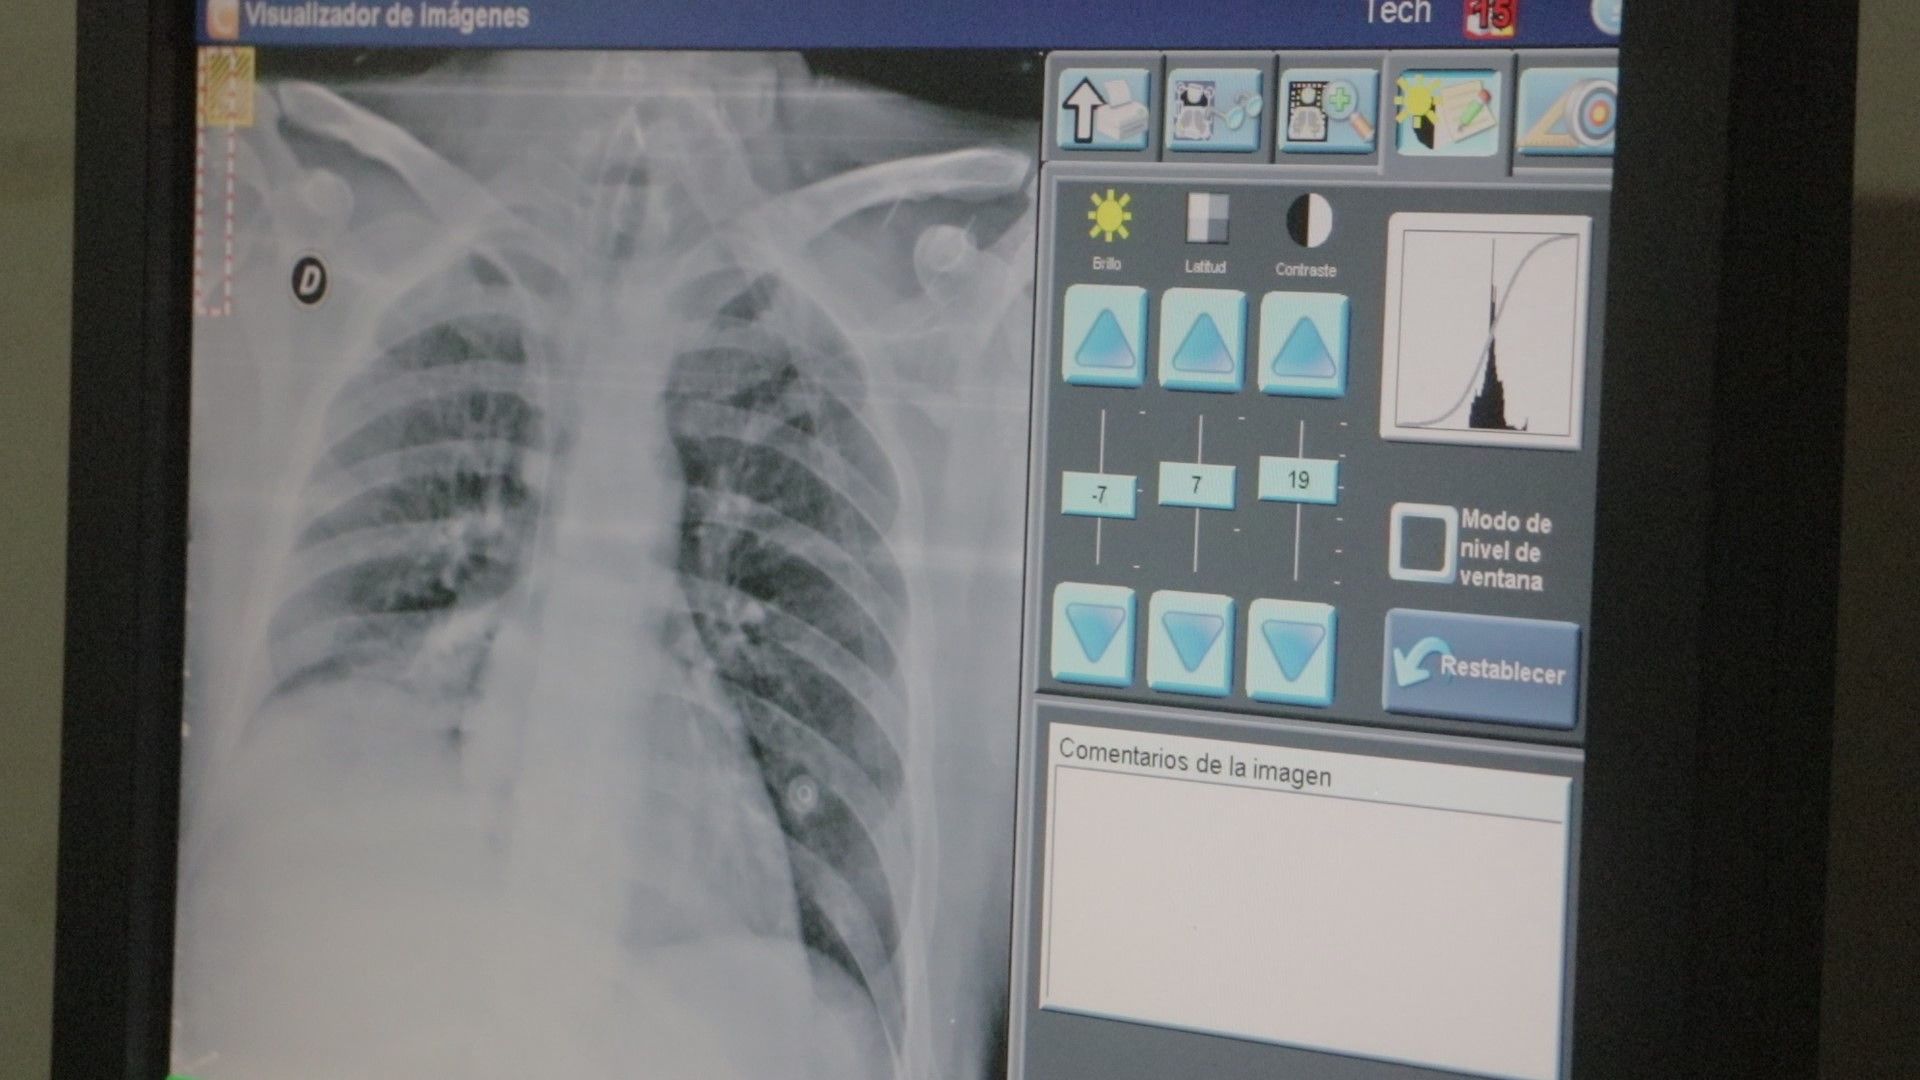

Es un programa de intervención multidisciplinaria para pacientes con enfermedades respiratorias crónicas. Participan neumonólogos, kinesiólogos, licenciados en salud mental, y, en ciertos casos, cardiólogos y nutricionistas.

La Dra. Susana Azcona, del Servicio de Neumonología del Hospital Escuela indicó que la jornada brindará información sobre el programa, su funcionamiento y los beneficios para pacientes con EPOC, enfermedades intersticiales, EPI, hipertensión pulmonar y secuelas pulmonares.

“Se discutirán síntomas como disnea y limitaciones en la vida diaria, y se destacará la importancia de la rehabilitación para mejorar la calidad de vida”, dijo la profesional